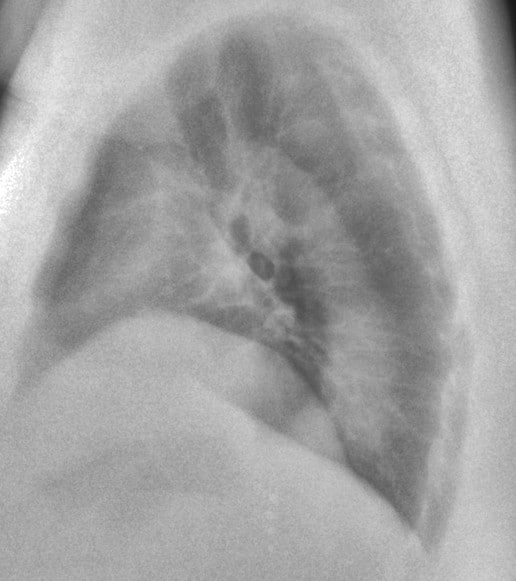

This 67-year old female patient presented to the ER with shortness of breath, in conjunction with chronic pain in her posterior thoracic region upon taking a large breath in. The reading radiologist noticed a suspicious mass-like opacity in the Lateral view. The radiologist stated that, thanks to the DE images, they could they tell the opacity wasn’t a lung mass, but instead far less concerning bony outcroppings from the thoracic vertebrae.